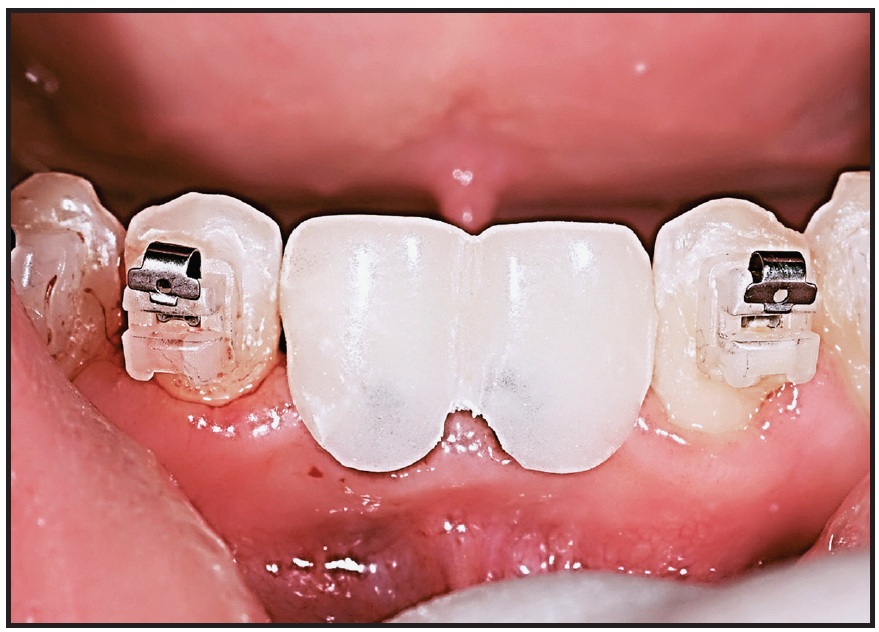

Both arches were bonded with .022" Tweemac-prescription Quicklear*** brackets. After 24 months of orthodontic treatment, the overjet and overbite were corrected, and Class I canine and molar relationships were achieved (Fig. 5).

Fig. 5 After 24 months of treatment with .022" Tweemac-prescription Quicklear*** brackets, anterior deep bite corrected and space gained for restoration of lower central incisors.